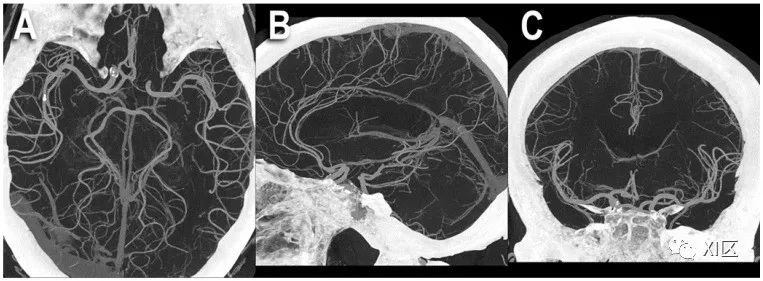

头部PCCT血管造影:三维电影容积渲染显示。图中显示的是100 μm超高分辨率的PCCT脑血管造影(源数据集;矩阵1024×1024;层厚/增量0.2/0.1mm;卷积核Bv60;辐射剂量与使用同类第三代双源CT进行的同等头部CT血管造影相当),使用了容积三维最大密度投影(MIP) (A)和电影容积渲染(B)。值得注意的是,显示的小动脉血管密度大幅增加。

头部PCCT血管造影:MIP容积显示。图中显示的是在三个主要平面:轴向(A)、矢状面(B)和冠状面(C)使用厚片三维最大密度投影(MIP)进行的100 μm超高分辨率PCCT脑血管造影(源数据集;矩阵1024×1024;层厚/增量0.2/0.1mm;卷积核Bv60;辐射剂量与使用同类第三代双源CT进行的等效头部CT血管造影相当)。值得注意的是,所显示的小动脉血管密度和可视段长度大幅增加;(A)为大脑后动脉和中动脉,(B)为大脑前动脉,(C)为大脑中动脉。Symons等人对头颈部主要血管的人体研究比较了PCD技术和EID技术,发现前者在图像噪声(比EID低9.1%)和图像伪影方面表现更好。